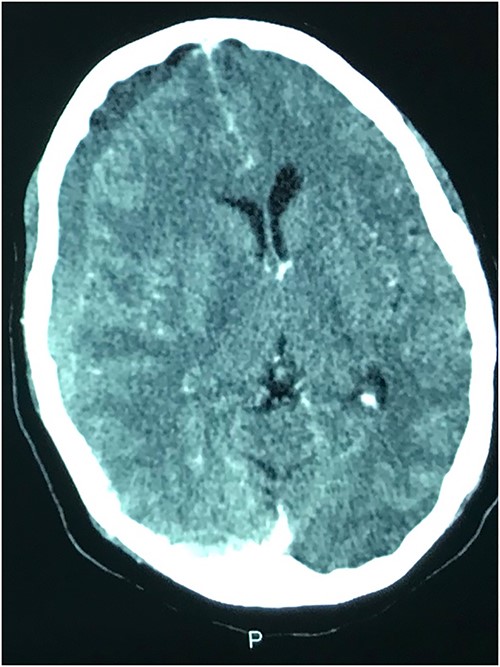

Case 3 – left isolated foot drop

A 78-year-old man with a 1-week history of headaches and dragging of the left foot. He had fallen in the bathroom 6 weeks prior to presentation. He had no other symptoms. Examination was unremarkable except for a left-sided foot drop with increased ankle jerk reflex. Brain CT done revealed a right-sided fronto-parieto-temporal CSDH (Figs 3 and 4). He had burr hole drainage and was discharged 3 days later to continue physiotherapy at home. At 4 weeks follow-up, his symptoms had completely resolved.

While few reports of bilateral lower extremity weakness have been reported with CSDH, unilateral foot drop is extremely rare. Two previous cases of isolated foot drop from CSDH have been reported, Sengupta et al. [17] and Weisberg [18]. Direct cortical compression of the motor foot area of the homunculus against the falx cerebri is the likely explanation in this scenario given the large right hemispheric CSDH. While the clinical suspicion of an intracranial lesion was considered due to raised ankle reflex, a diagnosis of CSDH before imaging was not entertained because of the rarity of isolated foot weakness.